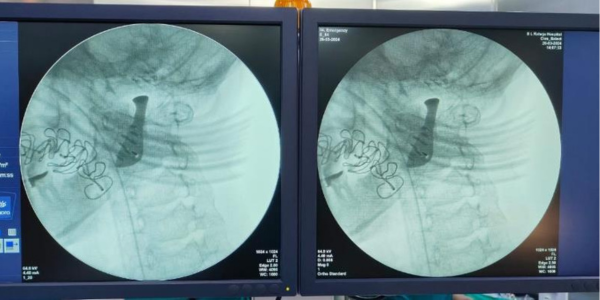

The patient-specific TMJ implant, manufactured under ISO 13485 guidelines by 3D Incredible, exemplifies a meticulous approach to medical innovation.

Designed with Ti6Al4V-ELI grade 23 for biocompatibility and anatomical precision, the implant not only facilitated reduced operation time but also ensured a perfect fit without further adaptations in the operating theatre. Read more